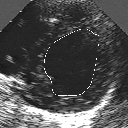

DETECTION AND TRACKING OF ANATOMICAL STRUCTURES USING DEFORMABLE TEMPLATES AND A NOISE MODEL ESTIMATION IN AN ECHOGRAPHIC SEQUENCE

In this work, we present a new method to shape-based segmentation of deformable anatomical structures in medical images and validate this approach by detecting and tracking the endocardial border in an echographic image sequence. To this end, a global prior knowledge of the endocardial contour is captured by a prototype template with a set of admissible deformations to take into account its inherent natural variability over time. In this approach, the data likelihood model rely on an accurate statistical modeling of the grey level distribution of each class present in the image. The parameters of this distribution mixture are given by a preliminary estimation step which takes into account the distribution shape of each class. Then the tracking problem is stated in a Bayesian framework where it ends up as an optimization problem. This one is then efficiently solved by a genetic algorithm combined with a steepest ascent procedure. This technique has been successfully applied on synthetic images and on a real echocardiographic image sequence. This method seems to be particularly well suited to handle ultrasound images with strong speckle noise on which edge information cannot be exploited. Finally, the local and global minimization procedure we propose is fast, robust and do not require initialization of the template close to the desired solution. Initialization may be defined at random, leading to segmentation and tracking procedure that are completely data driven. (slides)

Figure 1:   Tracking of the endocardial contour in a medical echographic sequence at different time frames during the cardiac cycle. From top left to bottom right : frame 1, 4, 6, 9, 12, 13, 18, 20, 27, 30, 35, 40, 41, 44, 46.